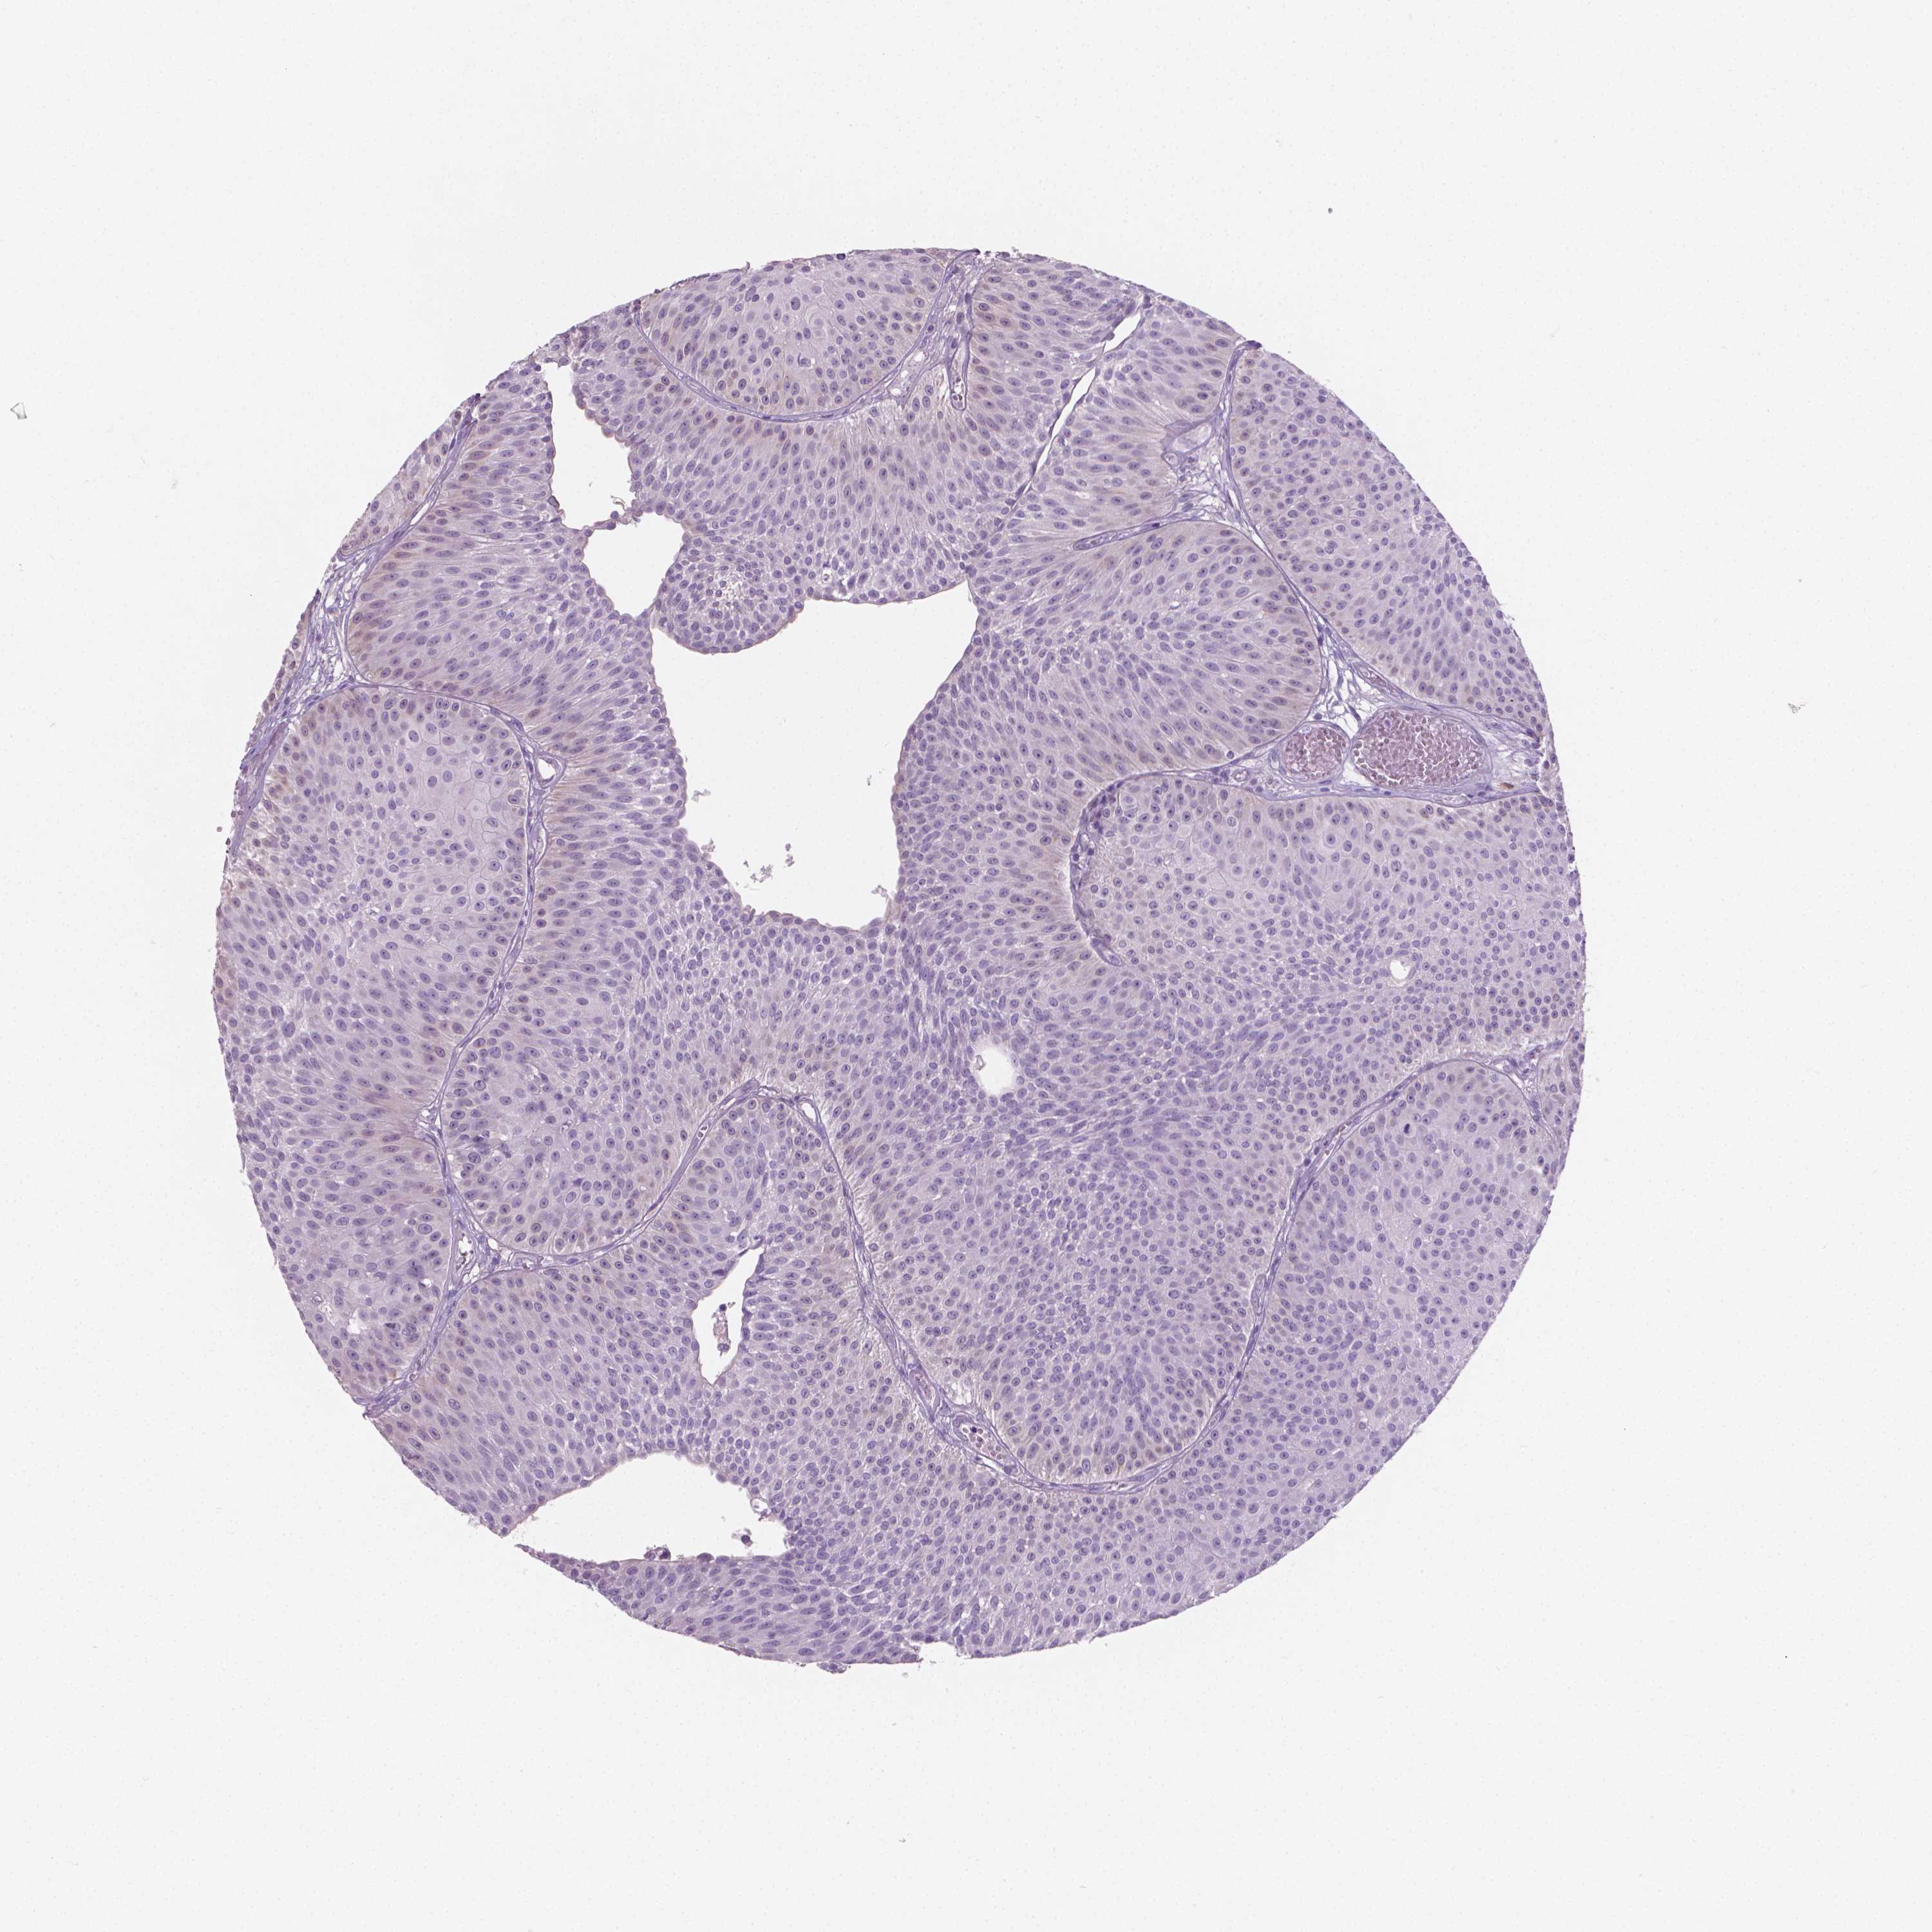

UROTHELIAL CANCER - Protein expressioni

A mouse-over function shows sample information and annotation data. Click on an image to view it in a full screen mode. Samples can be filtered based on level of antibody staining by selecting one or several of the following categories: high, medium, low and not detected. The assay and annotation is described here.

Note that samples used for immunohistochemistry by the Human Protein Atlas do not correspond to samples in the TCGA dataset.

Antibody stainingi

Antibody staining in the annotated cell types in the current human tissue is reported as not detected, low, medium, or high, based on conventional immunohistochemistry profiling in selected tissues. This score is based on the combination of the staining intensity and fraction of stained cells.

Each image is clickable and will lead to virtual microscopy that enables deeper exploration of all samples and also displays staining intensity scores, fraction scores and subcellular localization as well as patient and tissue information for each sample.

Antibody HPA023313

Antibody HPA064826

Staining

High

Medium

Low

Not detected

Intensity

Strong

Moderate

Weak

Negative

Quantity

>75%

75%-25%

<25%

None

Location

Nuclear

Cytoplasmic/membranous

Cytoplasmic/membranous,nuclear

Urothelial carcinoma, High grade

Urothelial carcinoma, NOS

Urothelial carcinoma, Low grade